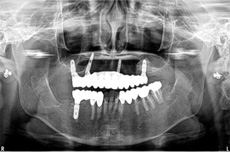

オールオン4の治療例:1

治療前

治療後

オールオン4の治療例:2